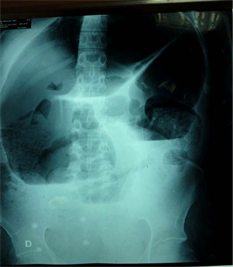

The imaging examinations were dominated by the ASP X-ray performed in 86 patients or 89.6%. She observed hydro-aerial levels in 83 patients or 96.5% (Table 1, Figure 1 and Figure 2).

Figure 1. Thoraco-abdominal X-ray and ASP from the front, patient standing, showing centro-peripheral hydro-aerial levels wider than high of hail origin.

These NHAs were wider than tall in 35 patients or 40.7%; higher than wide in 20 patients or 23.3% and mixed in 32.5% (Table 1, Figure 1).

The hydro-aerial levels typically presenting folds of haupstrations in 44.8% and folds of connivent valves in 55.2% (Table 1, Figure 2).

The central distribution of NHA was found in 55.2% of our patients compared to a peripheral distribution in 44.8% of cases (Table 1).